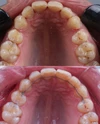

Diş Çapraşıklığı